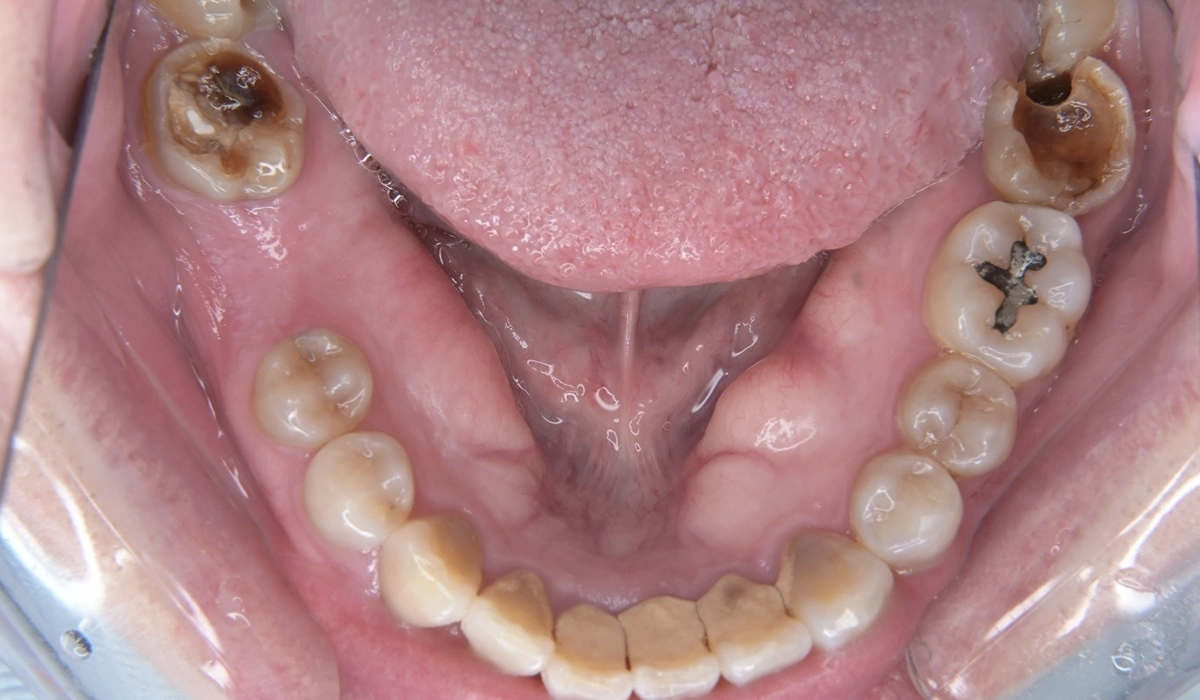

治療中の写真がこちらになります。

カリエス除去後に隔壁の作製を行い、ラバーダムシートによる環境整備を行って根管治療を行いました。

当院では根管治療においてイニシャルトリートメントこそ最重要と考えています。ここを間違えなければ5年生存率90%、10年生存率80%という世界的な統計報告を十分達成可能と考えています。